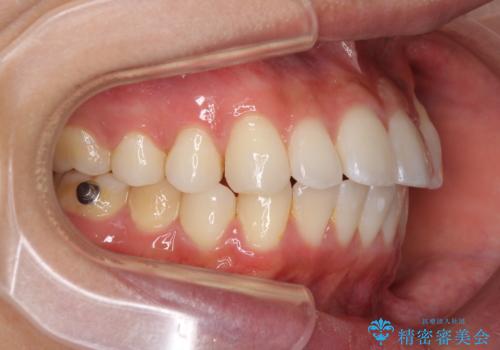

八重歯と奥歯のクロスバイト 上顎骨を拡大してインビザラインで矯正

- 八重歯を気にして来院された患者様です。

八重歯が著しいため、抜歯矯正も視野に入れて検討しましたが、臼歯の咬合関係は正常に近かったので、非抜歯矯正で進める方針としました。

上顎骨の幅が狭く、奥歯がクロスバイトとなっていたため、急速拡大装置を用いて上顎骨を側方拡大し、八重歯を収めるスペースを獲得しつつクロスバイトを改善することとしました。

上顎骨を思い通りに拡大できたため、当初の計画通りに非抜歯矯正で仕上げることができました。